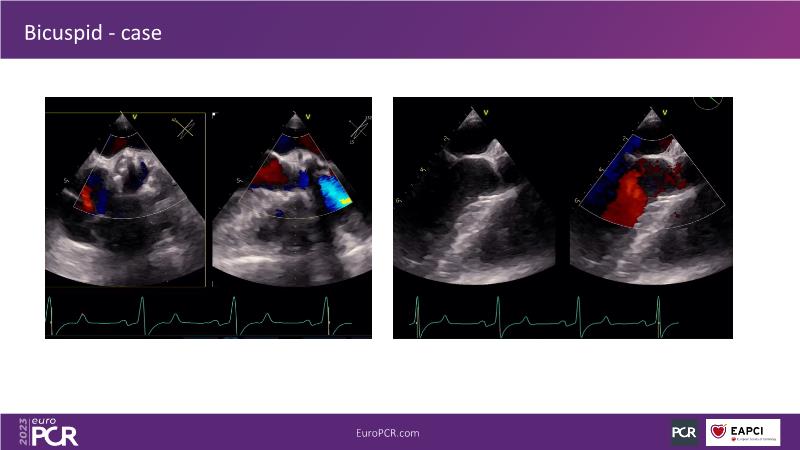

Discover the key factors to consider in selecting the optimal valve and implant technique for transcatheter aortic valve implantation (TAVI) to achieve optimal procedural outcomes. Gain insights into the impact of device choice and implantation technique on coronary access following TAVI and learn valuable strategies for tailoring your TAVI technique to complex scenarios, including bicuspid aortic valves, large and calcified anatomies, and ensuring coronary access.

- To learn how to tailor your TAVI technique to complex situations: bicuspid aortic valves, large, calcified anatomies and coronary access